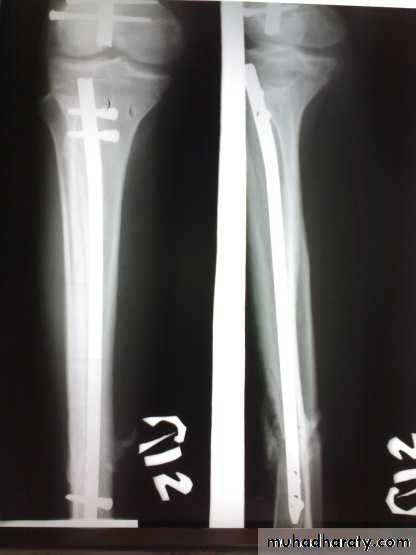

Skeletal fixation

Locked intramedullary fixation is the method of choice for diaphyseal (shaft) fractures.

Plate and screws for fractures near bone ends (metaphyseal) and for children with closed unstable fractures.

Principals of treatment

Treatment within hours or after several days until swelling subside by elevation and splintage.Anatomical reduction is a must to avoid later osteoarthritis.

Fibular fracture below tibiofibular lig. Ankle jt. is stable; reduce the fracture and immobilize in a cast.

Fibular fracture above tibiofibular lig. Ankle jt. is unstable; usually need internal fixation.

Medial maleolus fracture fixation

Postoperative management

Below knee cast for 4 wks in low-level injuries, and 6-8 wks in fractures treated by surgery.Complictions